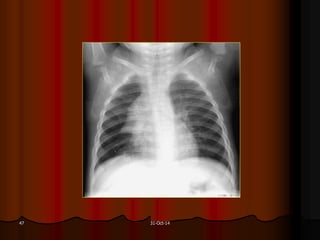

31-Oct-1446

31-Oct-1447